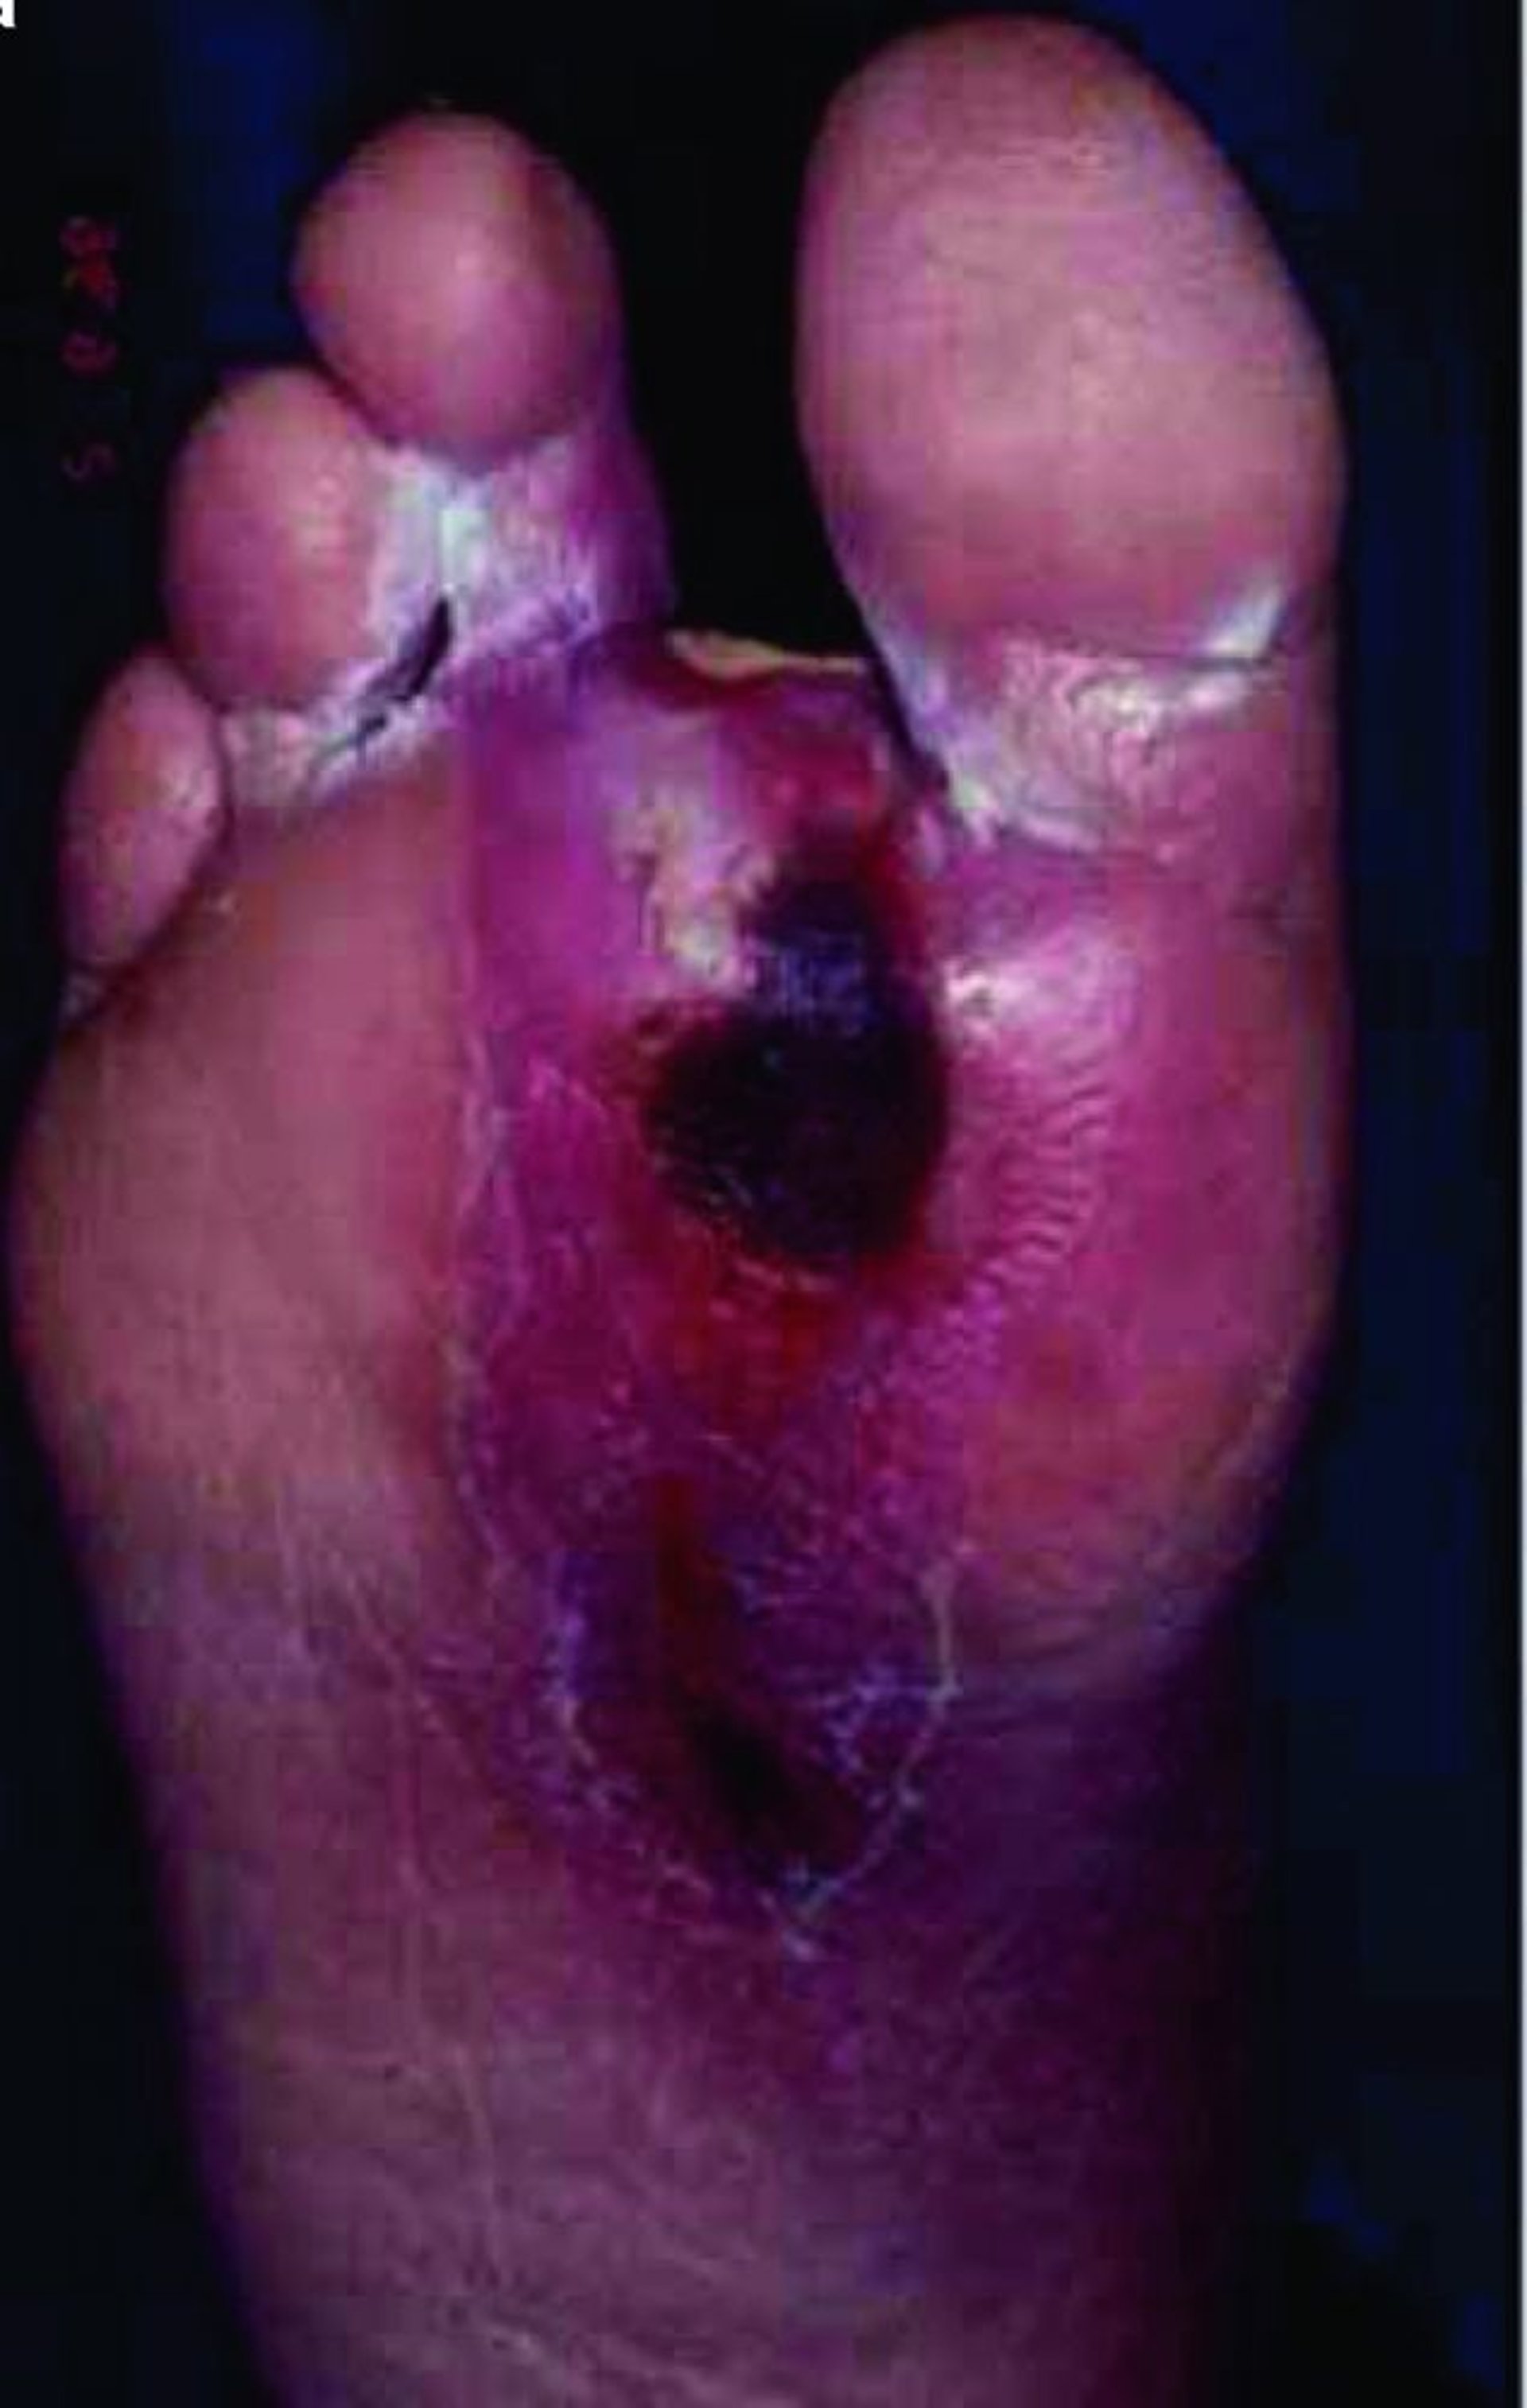

L’immagine mostra una grande ulcera sulla pianta del piede. I pazienti affetti da diabete sono particolarmente soggetti a ulcerazione dei piedi e delle gambe.